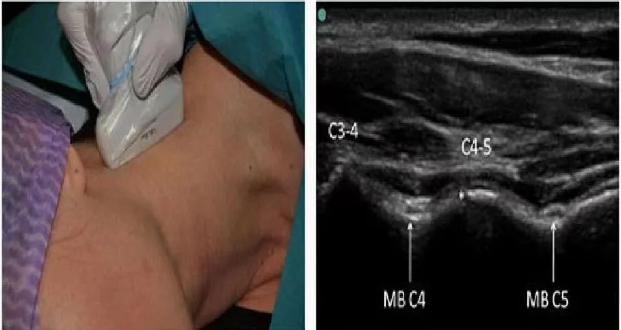

疼痛科团队,采用可视化技术在肌骨超声的引导下将消炎镇痛液注入脊神经后内侧支或第二颈椎背根神经节周围对其进行选择性阻滞。通过一次肌骨超声引导的注射治疗,患者头痛和颈肩部疼痛明显减轻、术后颈部僵硬情况即刻得到明显缓解。(供稿:疼痛科 崔家平)

超声可视化精准治疗 (上图)

超声扫查的脊神经位置

第二颈椎脊神经的超声显示图像